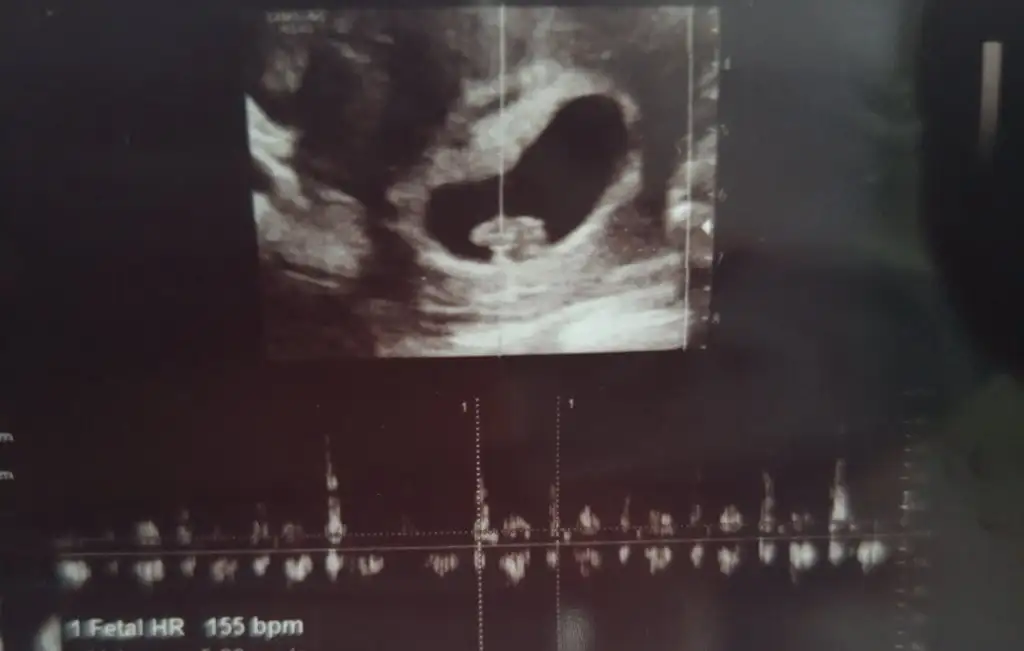

Canım,benim ki belli olmuyor mu? Bi bakar mısın?Aynen canım benim erkek, erkekler daha çabuk oluşuyor. Tabi istisnalar da var, ama yine de kız diyorumsağlıkla ve gönlünce inşallah

Kaç haftalık ve karından mıCanım,benim ki belli olmuyor mu? Bi bakar mısın?

6+3 karından canimKaç haftalık ve karından mı![]()